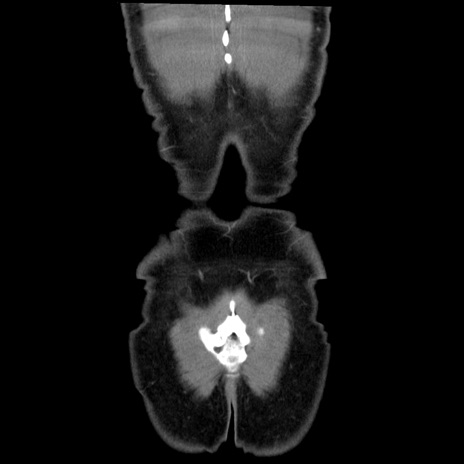

症例36(冠状断像)

【症例】20歳代 男性

【主訴】心窩部痛

【現病歴】今朝より上腹部痛あり。一旦軽快していたが再度出現したため救急要請。昨日夕に白身の魚を含む刺身を食べた。

【身体所見】BP 136/89mmHg、HR 74/min、BT 37.0℃、腹部:膨満、軟、心窩部に圧痛あり。反跳痛なし、筋性防御なし、腸雑音やや亢進あり。

【データ】WBC 17700、CRP 0.48

横断像